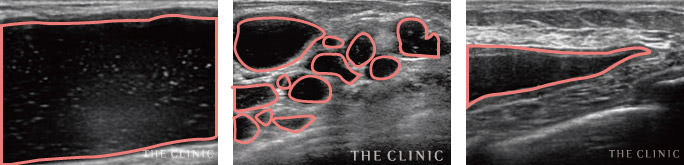

実際のエコー画像

溶解液注入   的確にしこりへ穿刺・注入

吸引・除去後   しこりの消失を確認

除去したヒアルロン酸   目視することで確実に除去

乳腺用エコーでしこりを診断

豊胸手術後のバストを診察する際、触診だけでは正確な情報は得られません。ましてやヒアルロン酸豊胸のしこりは数や大きさ、位置など様々な要素を的確に把握しなければ除去できません。

そのためTHE CLINIC では、全院に導入しているデジタル乳腺用エコー「エラストグラフィ」での検査を必ず実施。的確な診断を元に、治療を行っています。

ヒアルロン酸豊胸のしこりの多くは、注射器による処置で除去することが可能です。ただし、それはエコーでしこりを目視しながら、正確にアプローチできた場合のみ。触診だけを頼りに治療を行うクリニックもあるようですが、海外では「暗闇の手術」と呼ばれ、とても危険視されている行為です。

一方、THE CLINIC では、乳腺用エコー「エラストグラフィ」で目視しながら、的確にしこりを除去します。最短ルートでしこりを除去するため、体への負担を最小限に抑えることも可能です。